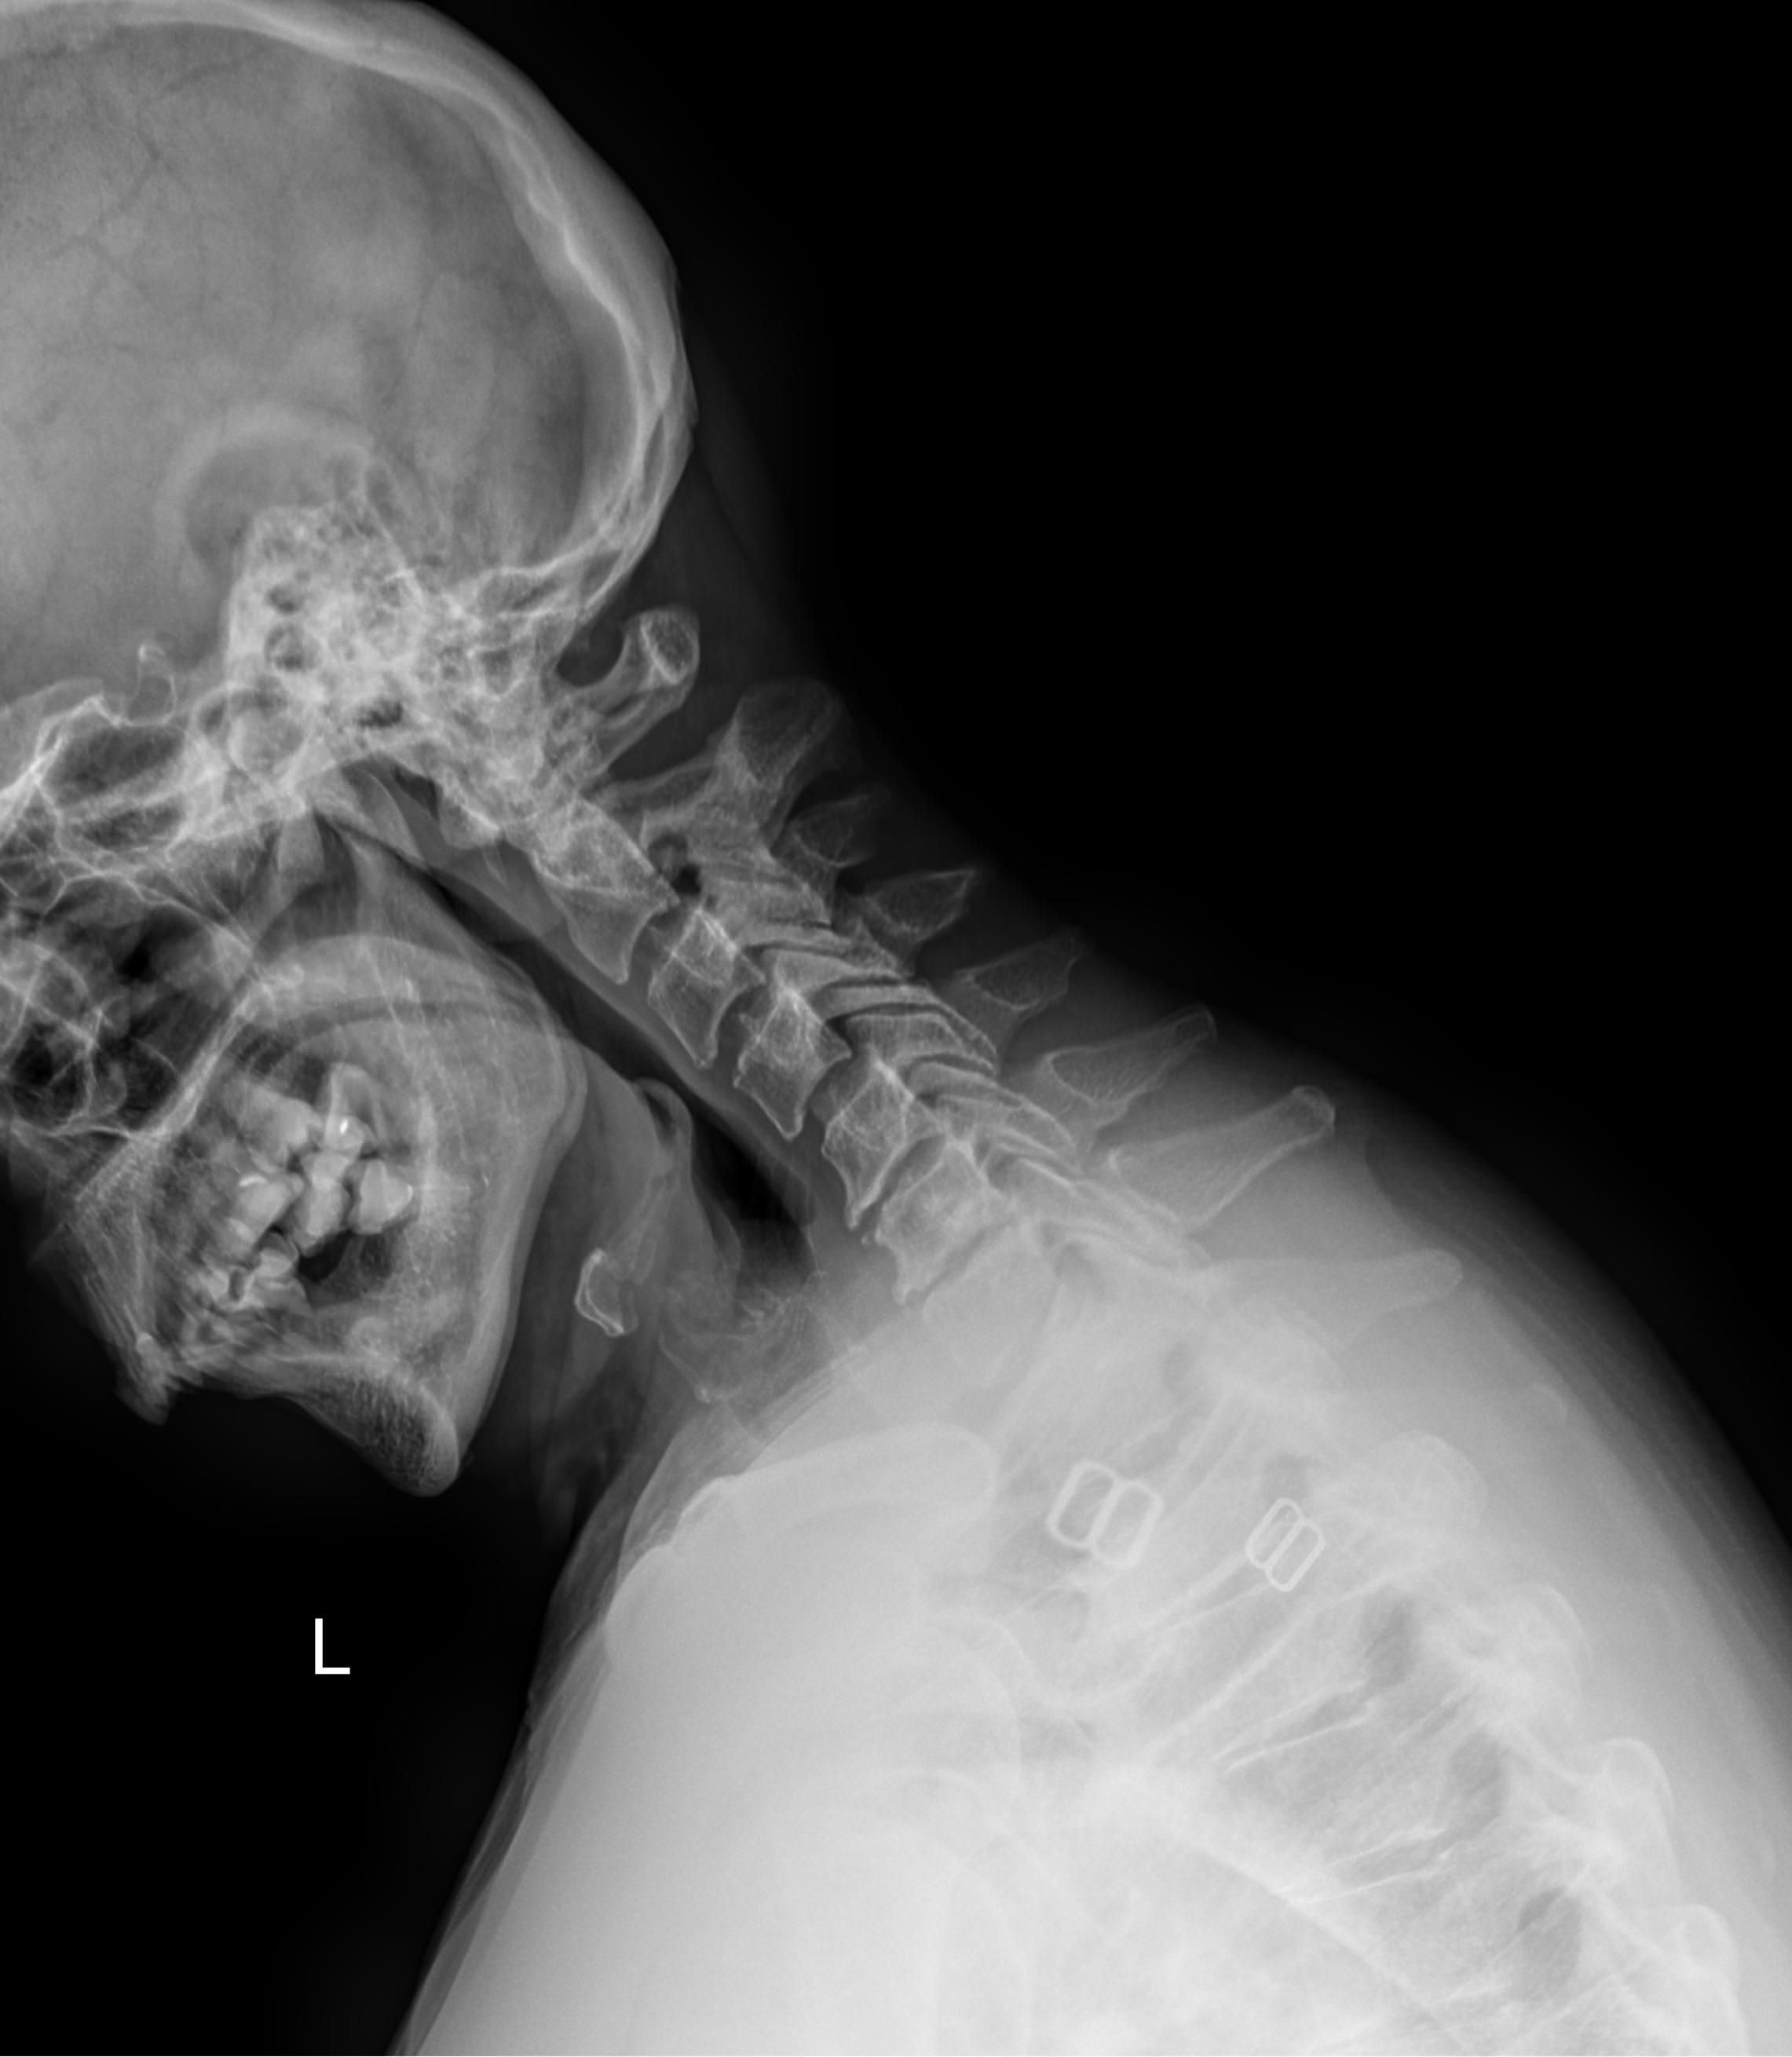

В качестве подготовки необходимо снять все металлические украшения с шеи и головы, расстегнуть пуговицы и надеть защитную накидку. Диагностика выполняется в положении стоя или сидя, всего делается 3 снимка:

• В боковой проекции ― строго боком к детекторной пластине;

• В условиях максимального разгибания головы назад;

• В положении максимального наклона головы вперед.